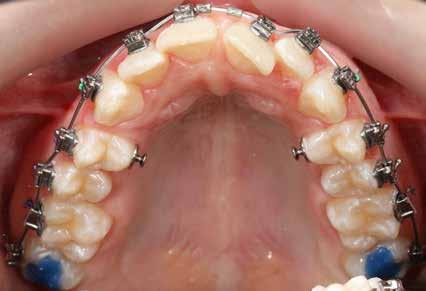

Ebben a cikkben egy 16 éves lánypáciens esetét szeretném bemutatni (1–7. képek)

A Pitts21-es fix készülékes kezelés során a harapásemelőket a felső nagyőrlő fogakra ragasztottuk, hogy a felső molárisok intrúziójával segítsék a harapás zárását (8. kép) Ún. keresztharapásos, majd később normál class 2-es gumihúzással (9–10. képek), továbbá az elülső fogakon alkalmazott ún. Rainbow harapás-záró gumihúzással (11. kép) korrigáltuk a jobb oldali teljes premolárisnyi distal-harapást, valamint az elülső nyitott harapást.

6 hónap után a nyitott harapás már nagyjából összezárásra került (12. kép)! A gumihordás a kezelés teljes hosszában folyamatos, éjjel-nappal, 22-24 órában az étkezések és az utánuk történő fogmosás kivételével.

A fix fogszabályozó készülék mindössze 16 hónapos kezelés után került eltávolításra! Páciensünk legnagyobb örömére állcsontműtét nélkül sikerült mind az arcesztétikai, mind a funkcionális rehabilitáció (13–18. képek)